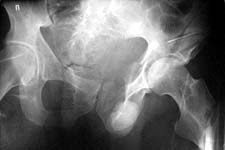

Today his left humerus and both ulnae were nailed. All closed. I attach two more images of the pelvis (inlet and Judet - i failed to find plain AP view). As his doctor told, he also has bilateral sciatic palsy, and severe calcaneus fracture. Anesthesologists tell that he will be ready for acetabular surgery not earlier than in a month. :-( He is in an external fixator with femoral extension. If femoral fragments looks aligned, and anyway fixator stays in place until the acetabular surgery, and maybe later, the femoral nailing today is probably for nothing.

Your fixator pins may burn some bridges for you in terms of approach for the acetabulum. This is clearly a complex acetabular fracture, and an extensile approach or more than one non-extensile approach may be required. I can't tell at this point, because you haven't supplied us with an adequate radiographic evaluation (2 Judet views, an AP pelvis and a CT scan). The inlet is helpful, but at first look, this appears to be an acetabular fracture, not a pelvic ring injury.

CR> 2. The pelvic pin sites, especially the left sided pins-their location/stability/contamination potential/need/and function?

Maybe something can be cleared with the attached image.

He has two column fracture with wing extension, but also a posterior ring injury.

You have shown an interesting iliofemoral external fixation.

Would it be possible to provide a schematic drawing of pin placement, frame construction and an idea of how long this takes to apply? Do the anterior pelvic pins traverse the wing extension of the both column fracture? Is there an xray in the frame? Thanks in advance for what info you can provide.